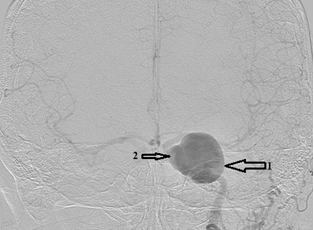

- Краткая информация о пациенте: Пациентка, 72 года. С 2016 года наблюдается по поводу аневризм левой ВСА. 15.09.2016 г. в ФГАУ «НИИ нейрохирургии им. акад. Н.Н. Бурденко» выполнена селективная церебральная ангиография. От оперативного вмешательства решено было воздержаться ввиду неблагоприятной анатомии несущего аневризму сосуда. В августе 2018 года выполнено МСКТ сосудов головного мозга, на которой выявлено увеличение размеров аневризмы кавернозного и супраклиноидного сегментов в сравнении с предыдущими данными от 30.03.2016 г. Была проконсультирована нейрохирургом клиники нейрохирургии ВМедА повторно. Было решено осуществить попытку эндоваскулярного лечения аневризм левой внутренней сонной артерии. Во время предоперационной подготовки при выполнении МСКТ-ангиографии брахиоцефальных сосудов была оценена анатомия ветвей дуги аорты и прослежен их ход в шейном отделе. Учитывая подтвержденные данные о неблагоприятной анатомии для трансфеморального доступа, было принято решение об изменении тактики хирургического лечения. Решено выполнить гибридное оперативное вмешательство: выделение левой общей сонной артерии, редрессацию патологических деформаций и эндоваскулярную имплантацию устройства, отклоняющего поток (FRED), на уровне аневризм левой внутренней сонной артерии. С учётом результатов генетического исследования на определение эффективности терапии препаратом Клопидогрел пациентке за неделю до госпитализации назначена двойная антиагрегантная терапия препаратом Плавикс 75 мг 1 раз в день и ТромбоАСС 100 мг 1 раз в день. Эффективность терапии оценена непосредственно перед началом оперативного вмешательства при помощи системы VerifyNow® — уровень подавления агрегационной функции тромбоцитов составил 36 %.

2 этап. По методике Сельдингера в левую ОСА установлен радиальный интродьюсер 6F. При помощи гидрофильного проводника Radifocus интракраниально введен направляющий катетер Fargo 6F. Затем при помощи микропроводника Traxcess14 область поражения – фузиформная аневризма кавернозного сегмента преодолена. Проводник заведен в левую СМА до уровня М3. Потом осуществлена замена микрокатетера на манипуляционный катетер Headway 27, кончик которого позиционирован в М1-сегменте левой СМА. Далее введено устройство, отклоняющее поток (FRED 4*32*26 мм). Стент позиционирован и имплантирован из-под бифуркации ВСА с перекрытием области поражения (3-х аневризм ВСА). Стент раскрыт полностью. При контрольной ангиографии левая ВСА проходима, стент прилежит к стенкам артерии; отмечается длительная стагнация контрастного вещества в гигантской аневризме; церебральные ветви проходимы, бессосудистых зон нет.